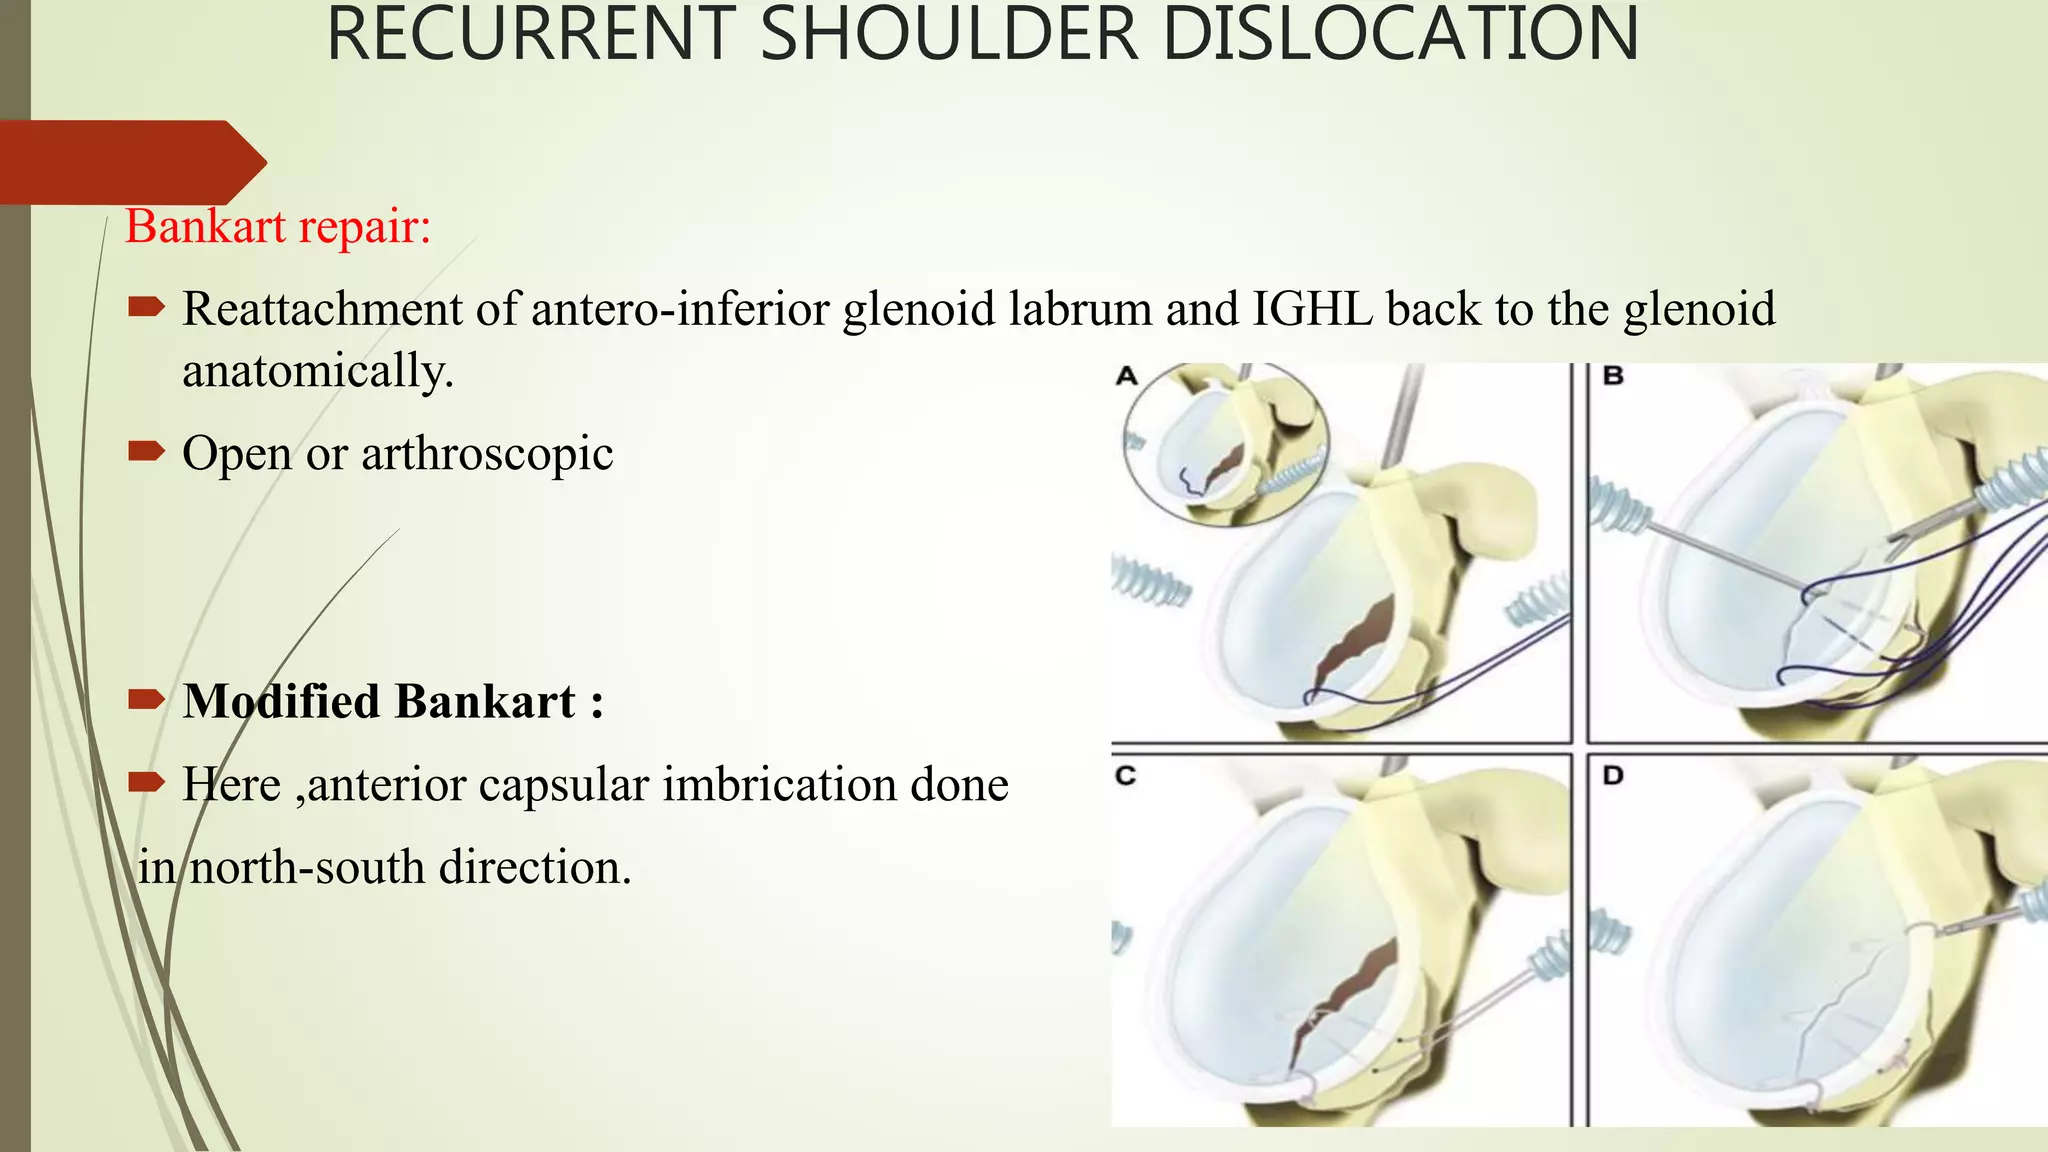

- Treatment involves closed reduction for most acute dislocations. Recurrent or complicated dislocations may require surgery and immobilization followed by physical therapy.